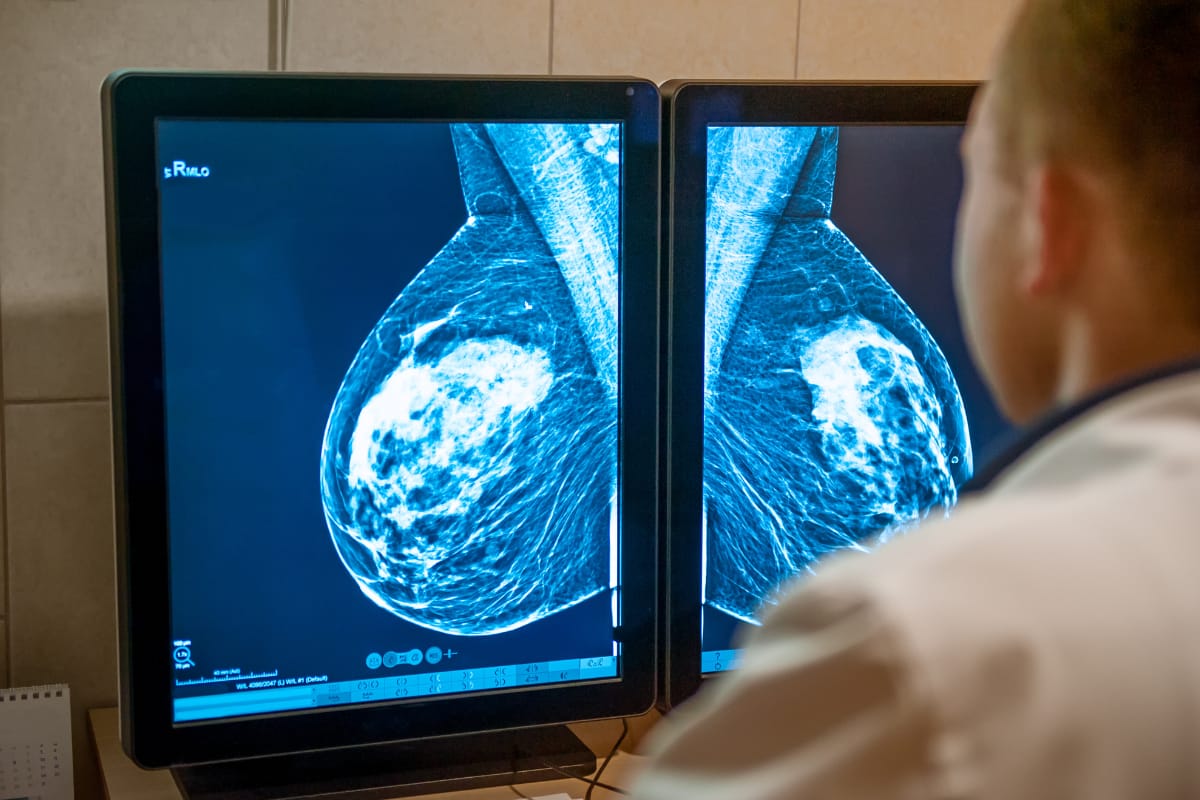

O governo federal sancionou a Lei nº 15.284, que amplia a oferta de mamografias pelo Sistema Único de Saúde (SUS) para mulheres com 40 anos ou mais, mesmo sem sinais ou sintomas. A publicação no Diário Oficial da União oficializou a mudança no rastreamento do câncer de mama, principal causa de óbito por câncer entre mulheres no Brasil.

Antes da alteração, o SUS ofertava o exame de rotina apenas para mulheres entre 50 e 69 anos, com intervalo recomendado de dois anos; pessoas mais jovens só tinham acesso em casos específicos, como histórico familiar ou alterações já detectadas. Com a nova norma, a testagem preventiva passa a ser garantida a partir dos 40 anos, aumentando potencialmente a detecção precoce da doença.

Dados citados pela lei e por órgãos de saúde registraram cerca de 20 mil mortes por câncer de mama em 2023. As projeções para 2025 apontam mais de 73 mil novos casos e mostram que a faixa entre 40 e 49 anos responde por cerca de 23% dos diagnósticos, reforçando a importância da ampliação do rastreamento.